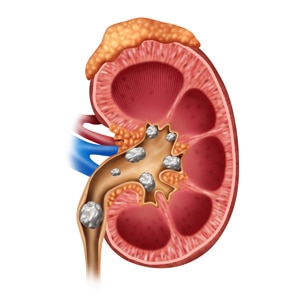

요로결석은 비뇨기관에서 소변의 성분들이 결정으로 변하여 돌이 형성되는 질병입니다.

요로결석 이란?

요로결석은 소변이 만들어져 배출되는 길인 요로에 결석이 생기는 질환입니다. 결석은 주로 칼슘, 수산염, 인산염 등의 무기질이 소변에 녹지 못하고 결정으로 뭉쳐져 생성됩니다.

요로결석은 신장, 요관, 방광, 요도 등 어디에서나 생길 수 있지만, 가장 흔하게는 요관에서 생깁니다. 요관은 신장에서 방광으로 소변을 운반하는 관으로, 지름이 약 5mm 정도입니다. 결석이 요관에 생기면 통증, 구역질, 구토, 혈뇨 등의 증상이 나타날 수 있습니다.